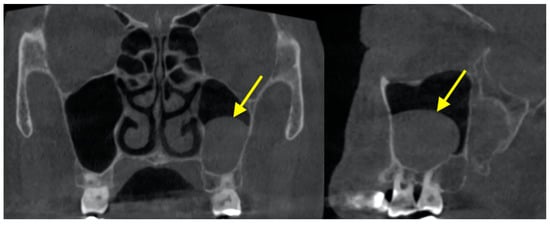

2.3. Hypoplasia